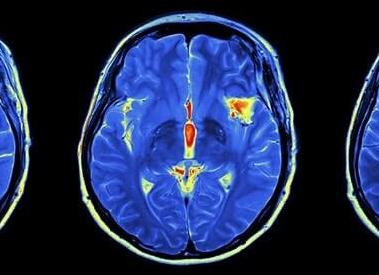

МРТ головного мозга с контрастом

В некоторых ситуациях применяется контрастное вещество. Это необходимо, когда обычное исследование имеет недостаточно четкую визуализацию или же требуется более детальное исследование определенных участков органа.

МРТ с контрастированием головного мозга позволяет выявить опухолевые образования на начальной стадии развития, когда они имеют незначительные размеры. Особое значение это имеет при наличии злокачественных опухолей. Данный вид диагностики помогает поставить точный диагноз при наличии аденомы гипофиза. Также данное исследование дает четкую картину распространения и структуры сосудистой системы головного мозга.